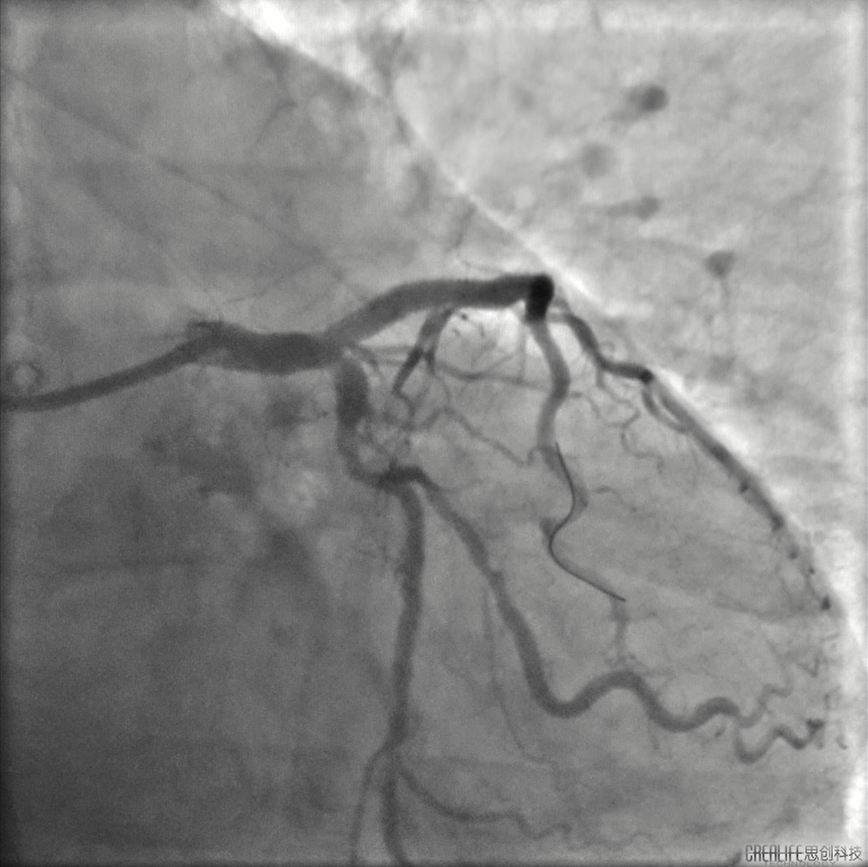

患者男,64岁,2022年6月5日急性下壁心肌梗死行介入干预,于右冠植入支架一枚,6月15日对左冠病变进行治疗。冠脉系统呈右侧优势型,右冠中段支架通畅。左主干大致正常,前降支近端至中段重度狭窄伴明显钙化。对前降支进行介入干预,以2.5*15mm球囊预扩张后,在前降支中段植入2.5*18mm Resolute支架,之后尝试在前降支近端植入 3.0*26mm支架不成功,经反复预扩张后,支架仍无法通过病变,血管内超声证实前降支近端可见环形钙化并重度狭窄。

庄晓东教授:该患者前次介入时未进行充分病变预处理即植入支架,造成支架膨胀不全,支架近端和远端仍残留钙化狭窄病变。尝试在近端病变植入支架不成功,即使使用切割球囊反复扩张,支架仍无法通过。旋磨可能需要通过支架对支架远端病变及近端病变进行处理,容易出现磨头嵌顿等并发症,冠脉内冲击波球囊钙化斑块碎裂术能有效打断环形钙化,对支架又不会造成额外破坏,且Shockwave球囊操作便捷,安全性好,是该病人目前治疗的最优策略。

胡洵教授:术前Oct可见前降支中远段严重钙化病变,部分节段呈360度钙化环,最大钙化厚度0.8 mm,中段原支架最小支架面积3.9mm2,支架膨胀率63%,支架外可见明显钙化斑块,近段已用3.0shockwave冲击波球囊进行30次脉冲冲击,钙化病变处可见多处断裂,最深断裂处可达 0.55mm,使用3.0shockwave球囊于中段原支架膨胀不良处进行50次脉冲冲击,2.5shockwave球囊于中远段钙化病变处进行30次脉冲冲击,再次复查Oct可见中远段钙化环出现多处断裂,中段原支架膨胀不良处支架面积明显改善,在前降支远段植入2.5支架,中段原支架内予以3.0高压球囊扩张,近段植入3.5支架并用3.5高压球囊扩张,最后复查Oct见远段支架最小面积 4.21mm2,支架膨胀率75%,中段原支架最小支架面积5.08mm2,支架膨胀率75%,近段最小支架面积 10.20mm2,支架膨胀率85%。

李怡教授:DISRUPT CAD III是一个前瞻性的多中心单臂研究,共入组431位患者。384 名原发性和继发性意向治疗数据纳入最终分析。结果显示:手术成功率达到99%,一年TVR为6%。CAD III证实了Shockwave IVL技术在复杂的冠脉钙化病变应用的安全性,围手术期并发症低;也证实该技术的有效性、易用性、学习曲线短,以及临床结果的一致性。